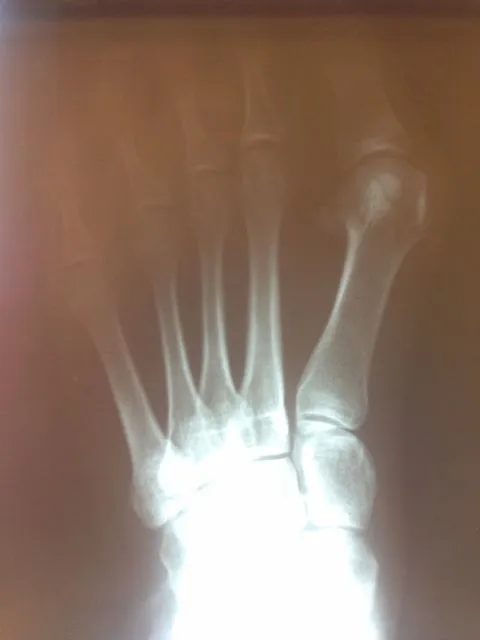

In the x-ray image below is a Hallux Valgus or what is more commonly known as a bunion deformity where the great toe is deviated towards the lesser toes causing abnormal structure which is a result of genetics, abnormal shoegear and abnormal mechanics will cause wearing of the joint and enlargement of the head of the long bone called the first metatarsal.

Post-surgical repair of the same patient bunion deformity with the great toe now in rectus (straight) position with surgically placed screws in the head of the first metatarsal that were used to secure fixation of the cut made across the bone to translate the head of the bone laterally in order to reduce the deformity. The screws will remain in place even after the bone heals.